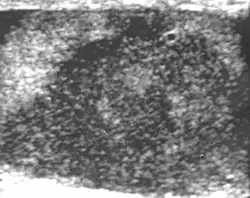

Patients with testicular lymphoma are usually old aged around 60 years of age, present with painless testicular enlargement and less commonly with other systemic symptoms such as weight loss, anorexia, fever and weakness. Bilateral testicle involvements are common and occur in 8.5% to 18% of cases. At sonography, most lymphomas are homogeneous and diffusely replace the testis [Fig. 7]. However focal hypoechoic lesions can occur, hemorrhage and necrosis are rare. At times, the sonographic appearance of lymphoma is indistinguishable from that of the germ cell tumors [Fig. 8], then the patient's age at presentation, symptoms, and medical history, as well as multiplicity and bilaterality of the lesions, are all important factors in making the appropriate diagnosis.